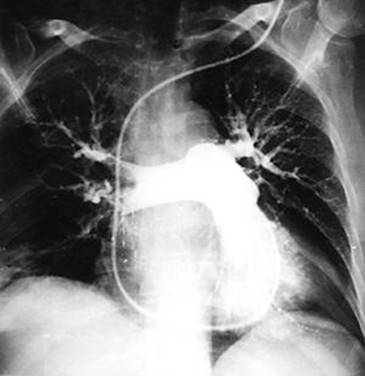

Рис. 4. Ангиопульмонограмма больного с массивной легочной эмболией. Имеется поражениеобеихглавныхлегочныхартерий

Рис. 5

63-летний мужчина с одышкой на протяжении 24 часов. Дефекты в ветвях левой нижней доли левого лёгкого (указано стрелками) свидетельствуют об острой эмболии.

При тромбоэмболии легочных артерий ангиопульмонографию выполняют экстренно на фоне интенсивных реанимационных мероприятий. При общей ангиопульмонографии рентгеноконтрастный препарат вводят (чаще через катетер) в верхнюю полую вену, правые предсердие и желудочек либо через локтевую, подключичную и бедренную вены с той или другой стороны. При селективной ангиопульмонографии под контролем рентгенотелевидения катетер проводят по нижней (через бедренную вену) или верхней (через вены верхней половины тела) полым венам, правому предсердию и желудочку в легочный ствол, куда и вводят рентгеноконтрастный препарат. Катетер может также быть введен в правую или левую легочную артерию и в сосуды меньшего порядка. При ангиопульмонографии при необходимости выполняют лечебные процедуры, например через катетер удаляют тромб легочной артерии или размягчают его ферментами.